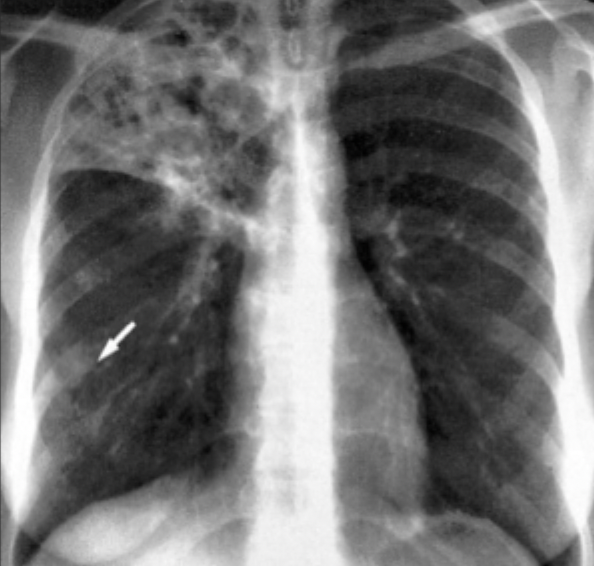

What is this ?

A

Primary TB

-Primary lung lesion (Ghon focus)

-Associated lymph node enlargement

lung focus + lymph nodes = Ghon complex